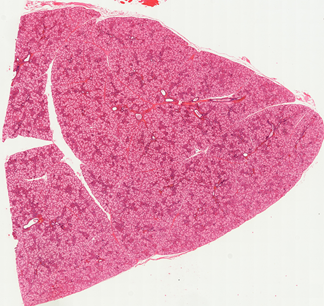

Oral Histology Slides

You may take a glance at the example photos of the available 36 slide below.

You may also download a complete list of oral histology slides for detailed information.